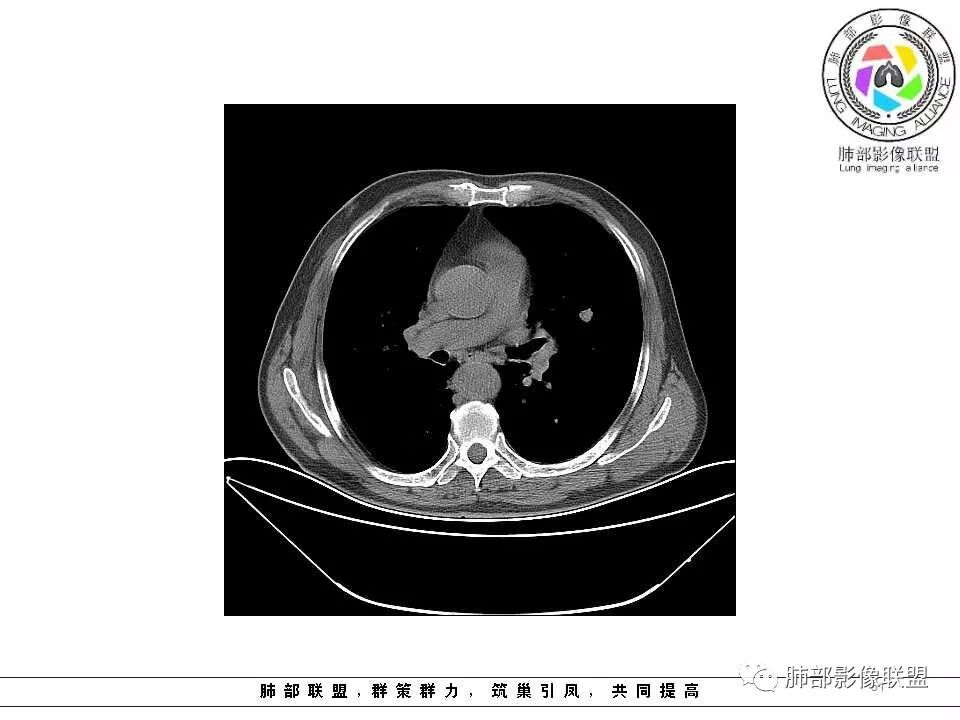

影像学特点:肺气肿背景下在大概一年的时间里出现了一个光滑的小结节,因为图像给的不是太薄,与支气管的关系判断不清,从结节周围出现斑片状炎症来判断,应该考虑结节位于支气管内,周围是阻塞性炎症,这样比较容易解释咯血

纵隔窗上似乎结节内可见点状高密度影,同时没有明显肿大淋巴结

老年男性,肺气肿背景,左肺上叶舌段病灶明显增大,变异膨隆,远端阻塞肺炎,考虑鳞癌。

老年男性,肺气肿基础。约一年时间出现左肺上叶舌段支气管近端结节影,远端斑片样阴影,边缘模糊。考虑近端恶性占位,远端有阻塞性炎症。

老年男性,两肺可见小叶中央型肺气肿,提示应该有抽烟史。2016年片,右肺门支气管稍模糊,考虑慢性感染,纵膈淋巴结稍大。但2017年左肺上叶新发占位,堵塞支气管,引起局部肺不张伴感染,且纵膈淋巴结较2016年变大,患者同时伴有咯血,考虑恶性。鳞癌?类癌?小细胞?

肺气肿背景,2016年左肺上叶上舌段见微结节,一年后左肺结节增大,密度均匀,边缘光滑、膨隆,似见小分叶,下舌段片状影,沿着支气管走行,内,老年患者,咯血1月。考虑恶性病变并阻塞性肺炎,鳞癌?注意鉴别结核。

前次片2016年4月20相应位置就有小点状病灶,2017-5-15呈结节影改变,边界膨隆,远端阻塞炎性改变,考虑肺癌,鉴别炎性结节!

后头看前片似乎当时腔内壁稍增厚一点